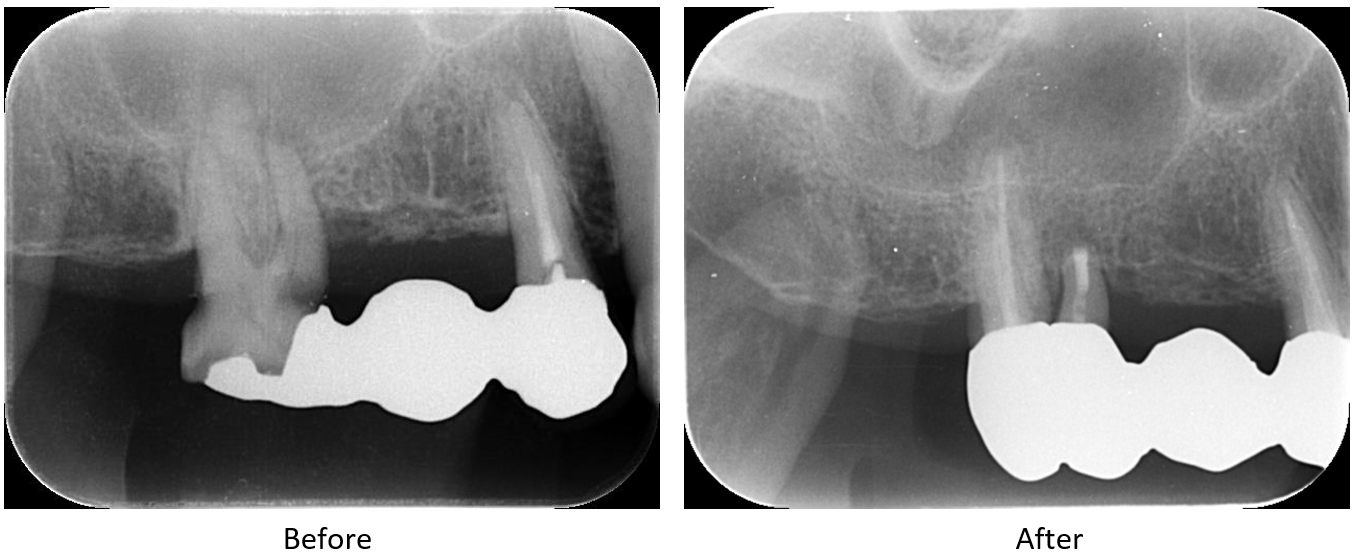

症例3

| 患者様データ | 80代 女性 |

| 来院時の主訴 | 「右上の歯が腫れた。」 |

| 医院の診断 | 慢性根尖性歯周炎 |

| 通院期間 | 6か月 |

| 来院回数 | 9回 |

| 治療費 | 総額:650,000円(税抜) 【内訳】 精密根管治療70,000円(小臼歯)+80,000円(大臼歯)+歯根端切除手術(大臼歯)100,000円(当院で根管治療を行なっているため差額分のみのご請求)、ファイバーポストコア20,000円×2、セラミックブリッジ治療360,000円 |

| リスクと副作用 | ①根管治療歯は長期的には破折するリスク ②長期的なメインテナンスが必要 |

| ここがこだわりのポイント!☝ |

患者様はインプラント治療や入れ歯治療に抵抗感が強く、自分の歯で食事をとりたいという希望がありました。MTAを使用した歯根端切除を行うことで、抜歯を回避することができました。 |